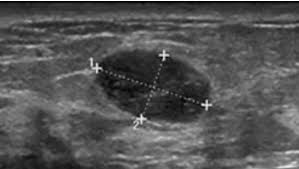

Ultrasound Characteristics of Phyllodes Tumors

• Rapid growth of breast lesions like the one seen above suggests that it is a phyllodes tumor:

• Although a giant fibroadenoma is another possibility

• The ultrasound image shows:

• An isoechoic, heterogeneous mass that contains cystic, fluid filled spaces, and is vascular on Doppler examination

• In most cases, benign phyllodes tumors have margins that are well-circumscribed, and a thin, echogenic capsule is demonstrable